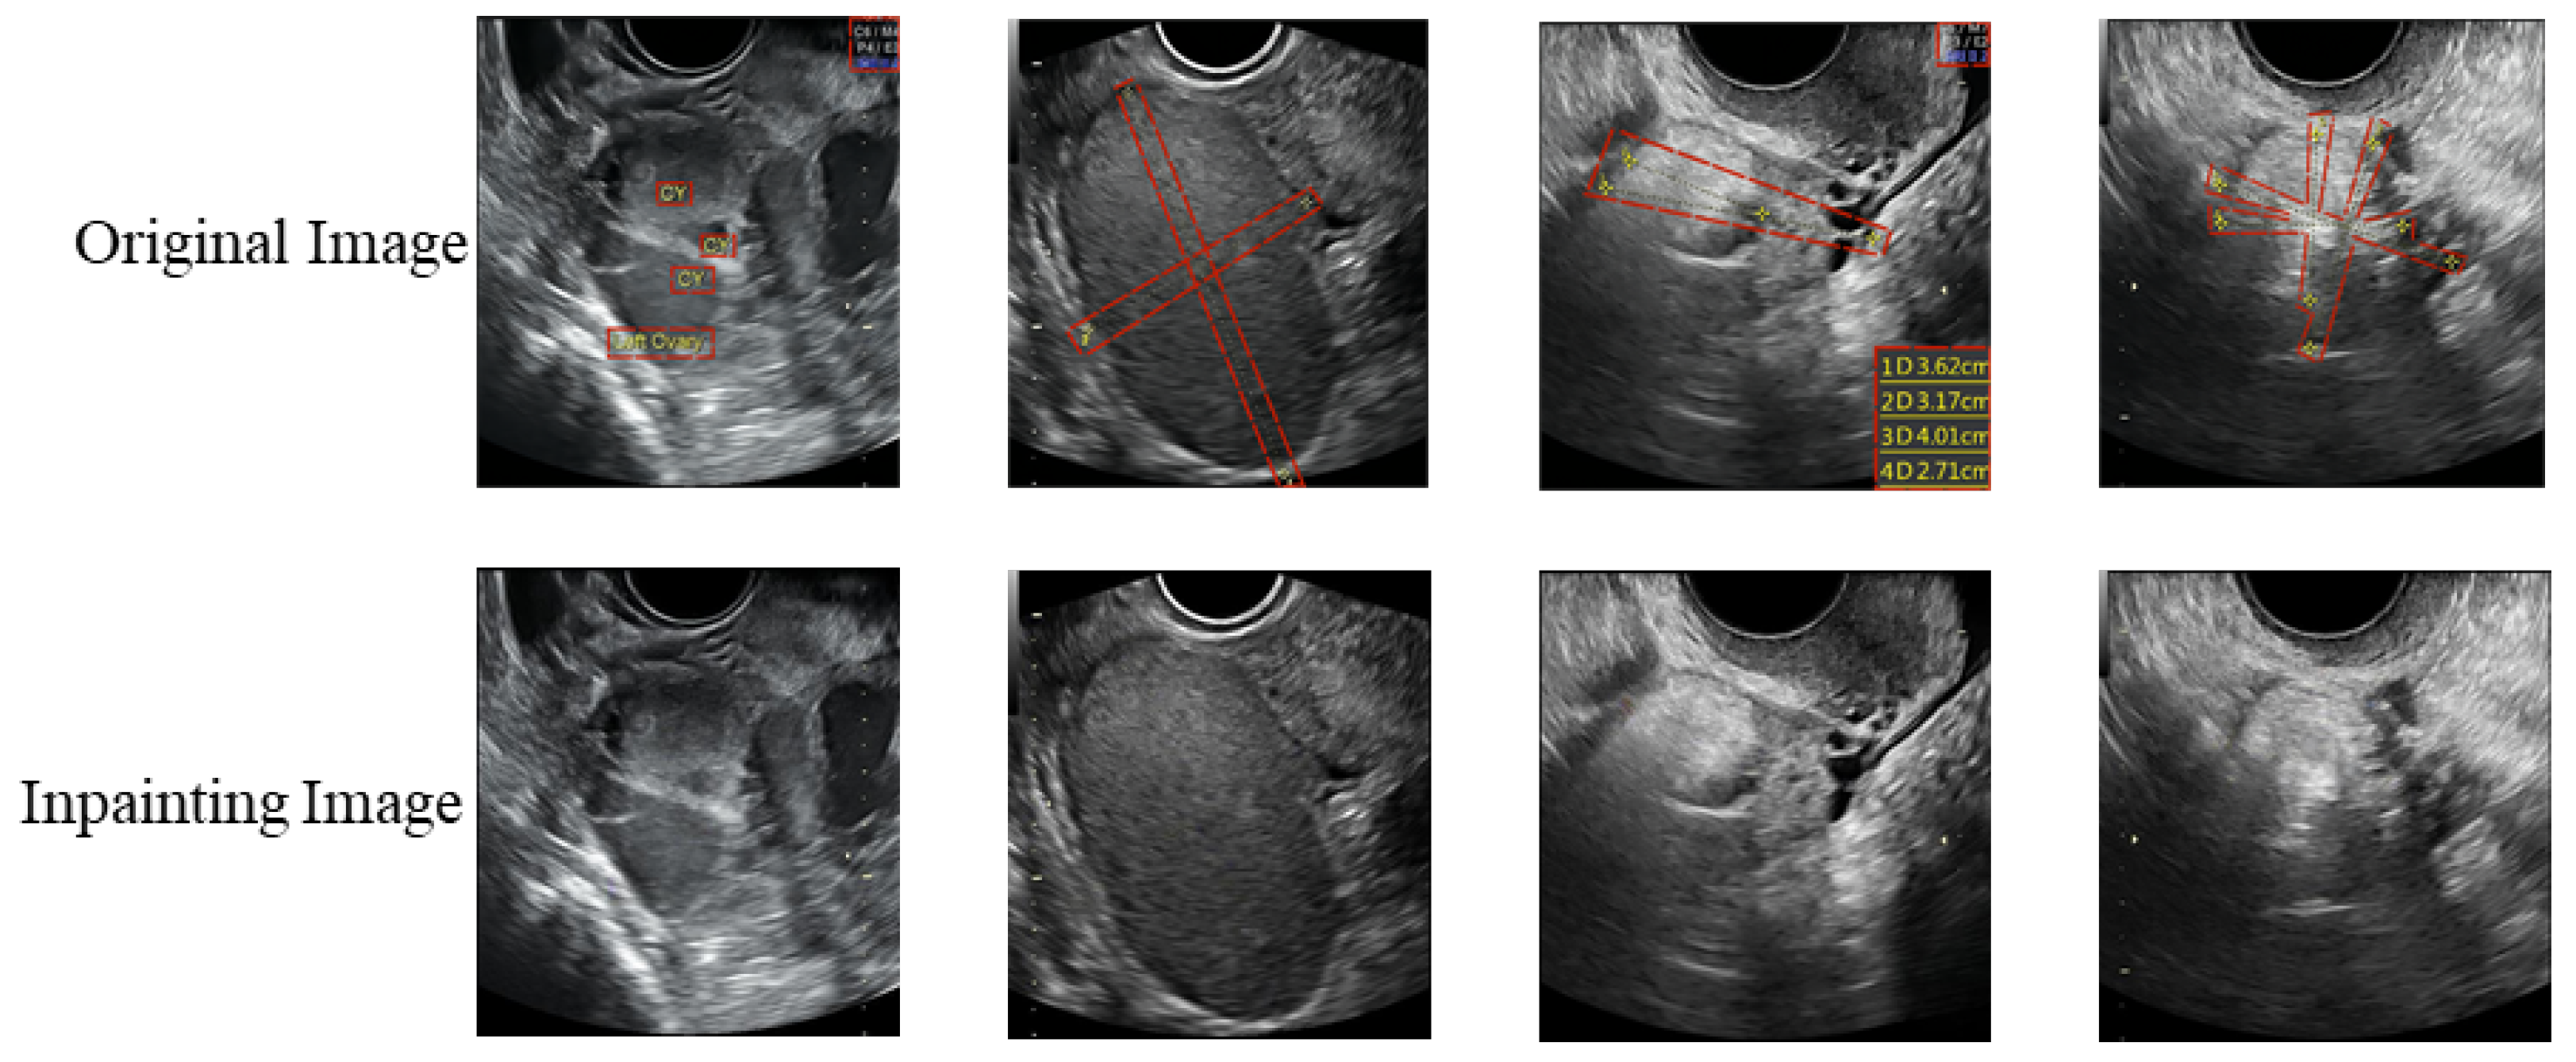

- We refined 1469 2D ovarian-tumor ultrasound images for irregular symbols and obtained binary masks to establish a 2D ovarian-tumor ultrasound image inpainting dataset.

3.1.1. Experiments on the Image Inpainting